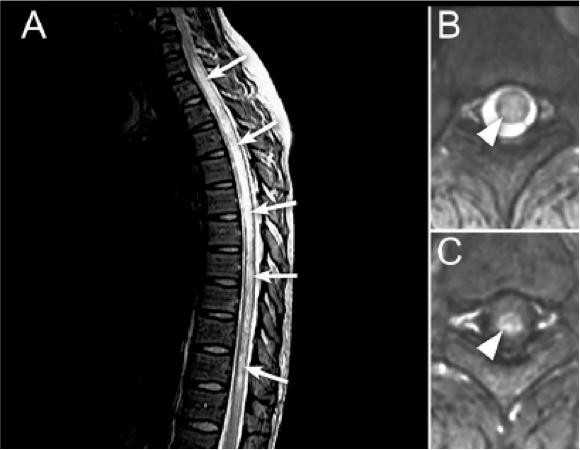

二、影像特征 1. NMOSD 脊髓MRI:长节段的脊髓炎(≥3个节段),呈中心分布,横贯性